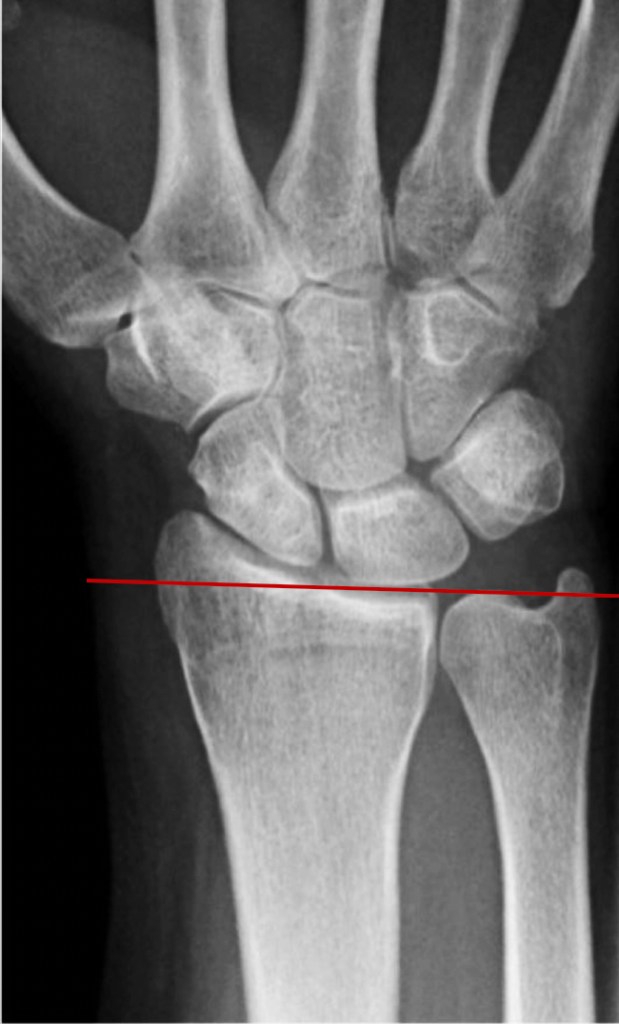

Biomechanics of the wrist – In patients with Kienbock’s disease, there is an increased incidence of the radius bone being slightly longer than the ulna at the wrist joint, or having an increased slope compared to normal at the wrist joint. These anatomical variants may lead to an increase in the pressure within the lunate bone and thus predispose to cutting off the blood supply.